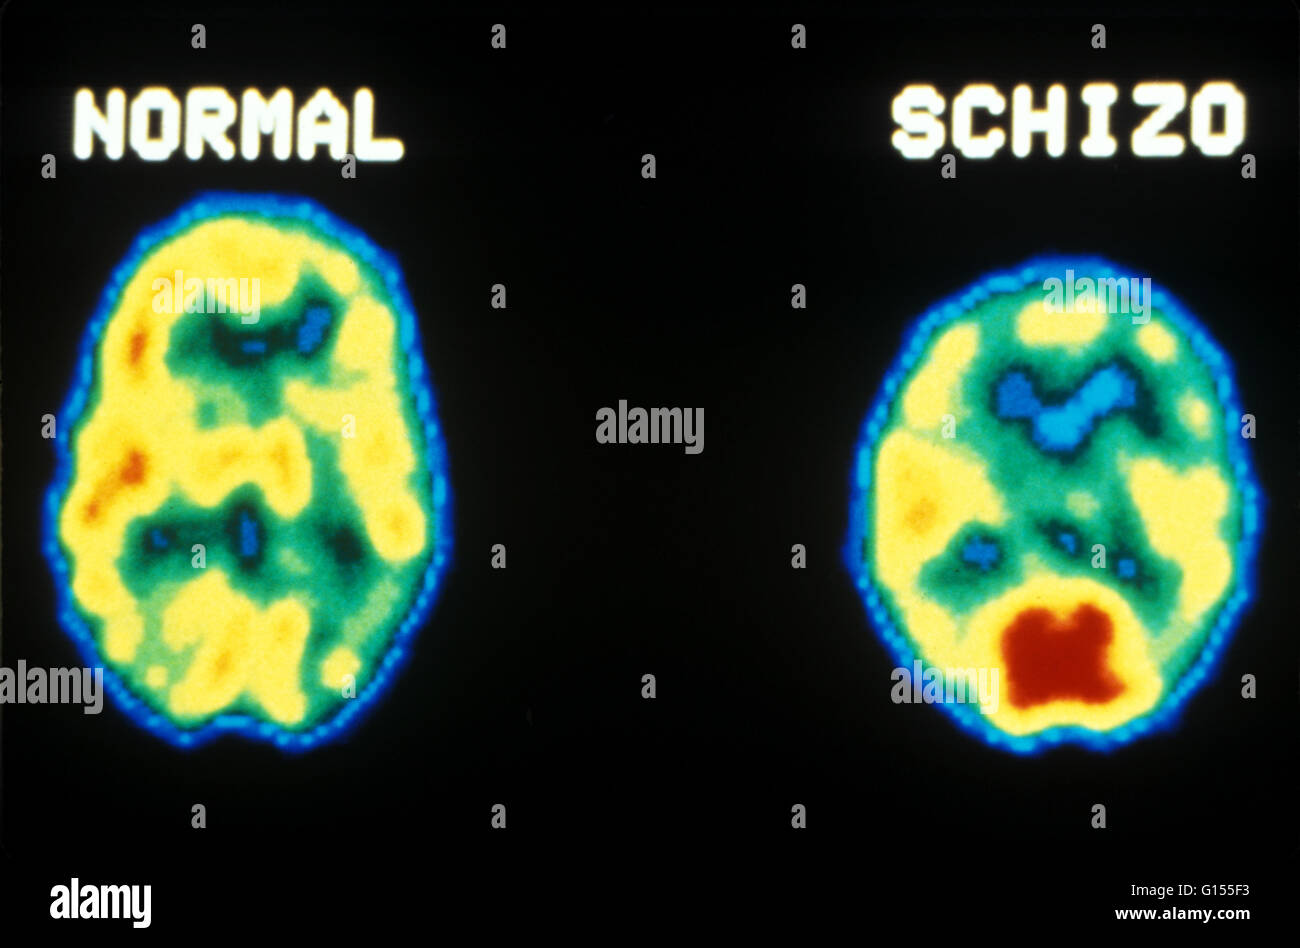

Pet Scan Brain Depression Can Mri Brain Scan Show Depression New mri scans may reveal previously unknown differences in the brains of people with depression. Magnetic resonance imaging (mri) studies support reduced brain volume in patients with depression compared to groups of healthy subjects, large. An mri scan could reveal what would work for you. And the technology is great at revealing damage from a stroke, or areas that light. Can Mri Brain Scan Show Depression.

An example of depression and normal brain by MRI. (Image is from Can Mri Brain Scan Show Depression The researchers say that their findings deepen. New mri scans may reveal previously unknown differences in the brains of people with depression. There are no molecular or imaging biomarkers widely accepted for the assessment of clinical depression. Mri scans have allowed researchers to peer inside the human brain. Magnetic resonance imaging (mri) studies support reduced brain volume in patients with. Can Mri Brain Scan Show Depression.